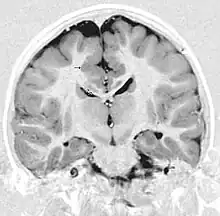

This child presented with seizures. The coronal true inversion recovery sequence shows thickened and disordered cortex in superior frontal and cingulate gyri bilaterally (arrow). There are small convolutions visible at the corticomedullary junction. The appearance is that of cortical dysplasia, with polymicrogyria more likely than pachygyria due to the small convolutions visible. There are also small foci of grey matter signal in the corpus callosum, deep to the dysplastic cortex (double arrows). These probably represent areas of grey matter heterotopia.